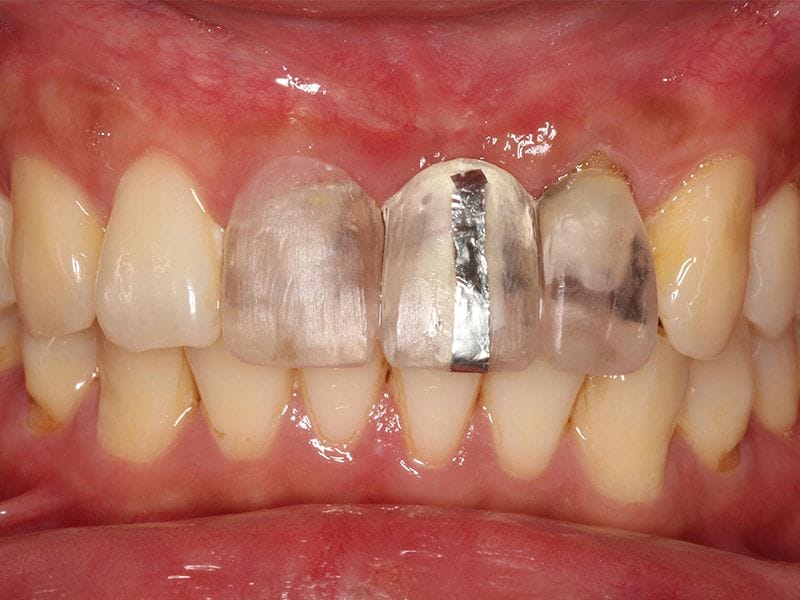

最終,我們以三顆全瓷冠假牙修復完成。我們確實也達到我們所設定的目標:在牙齒的顏色、長度寬度、牙齒之間和牙齦高度的協調性都很高。也相信 Mr.Wang 有了兼具功能、美觀的牙齒,一定更能展現充滿自信的笑容。

完成人工植牙後,與桃園全瓷美學專家沈志容醫師合作,以數位全瓷冠修復三顆前牙 完成的全瓷冠牙套顏色、細節逼真,前牙咬合時幾乎看不出差異

圖示:人工植牙手術前後X光片比較:(左)假牙拆除後,可見缺牙處兩邊的支柱牙結構破壞嚴重;(右)人工植牙手術後,完成全瓷冠假牙